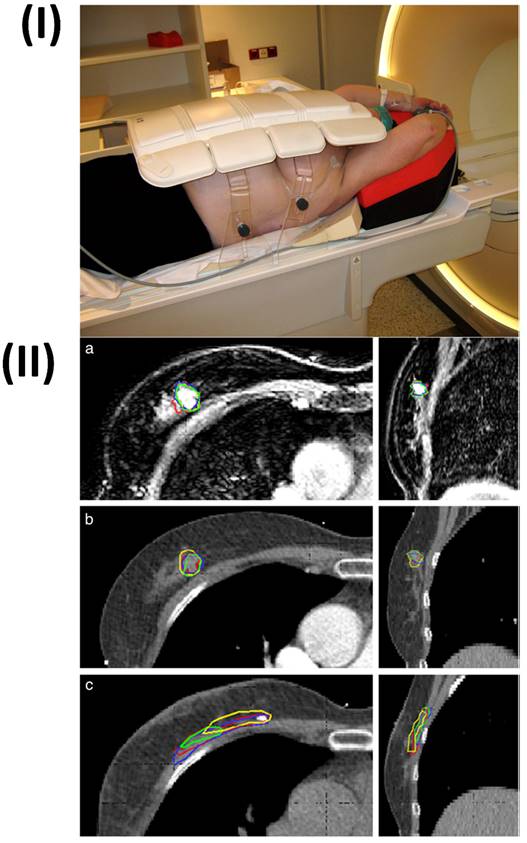

In a study, Lu et al. fabricated gadolinium hyaluronic acid nanoparticles. In this study the rabbit model was used, its knees were injected with gadolinium-hyaluronic acid nanoparticles, gadolinium-DTPA-hyaluronic acid, and gadolinium. After the injection, the knee was imaged using a coil-equipped Siemens Verio 3T MRI system. The signal intensity changed at the cartilage injury site after treatment with Gd-HA NPs, Gd-DTPA, and Gd-DTPA-HA are shown in Fig. 1II. After an hour of Gd-DTPA injection, the articular cavity's signal intensity increased, and the lesion image slightly improved, but the cartilage's contours still remained unclear. At 2 and 3 h after injection, the proximity of signal intensities between the cartilage and the injured areas was maintained. However, in the case of Gd-HA-NP and Gd-DTPA-HA groups after 1h of injection, intense signals were observed. Additionally, the MRI signals for the lesion and cartilage were substantially greater after 2 h after injection. The intensities of MRI signals were seen to be gradually dropped after 3 h of injection indicting the metabolization of contrast agents. This finding was consistent with the established MRI time frame of 2-3 h for cartilage assessment. Gadolinium-hyaluronic acid NPs penetrated the core of cartilage tissues and functioned as an effective MR imaging probe for the precise diagnosis of cartilage injury because of their ideal size and great affinity for ECM (Extracellular Matrix). The research revealed that the nanoparticles could be useful for MRI-based clinical cartilage injury identification [86]. Another study reported the fabrication of a new Gd-based nanoparticle for T1-weighted MR imaging called as dual-Gd liposomal agent. This agent combines the characteristics of core-encapsulated Gd liposomes (CGdL) and surface-modified Gd liposomes (SGdL) to deliver a large Gd concentration which increases signal intensity for each particle. The formulations SGdL, CGdL, and dual-Gd were given identical lipid doses of 200 mg/kg, resulting in equivalent blood levels of liposomes in vivo.

Figure 1

I) Illustration showing the use of Gd-HA NPs in MRI for the diagnosis of cartilage damage. II) In vivo MRI images of rabbit cartilage injuries after treatment with Gd-DTPA, Gd-DTPA-HA, and Gd-DTPA-NPs. Reproduced with permission from the ref. [86], Fig. 4 (Elsevier, 2020©).